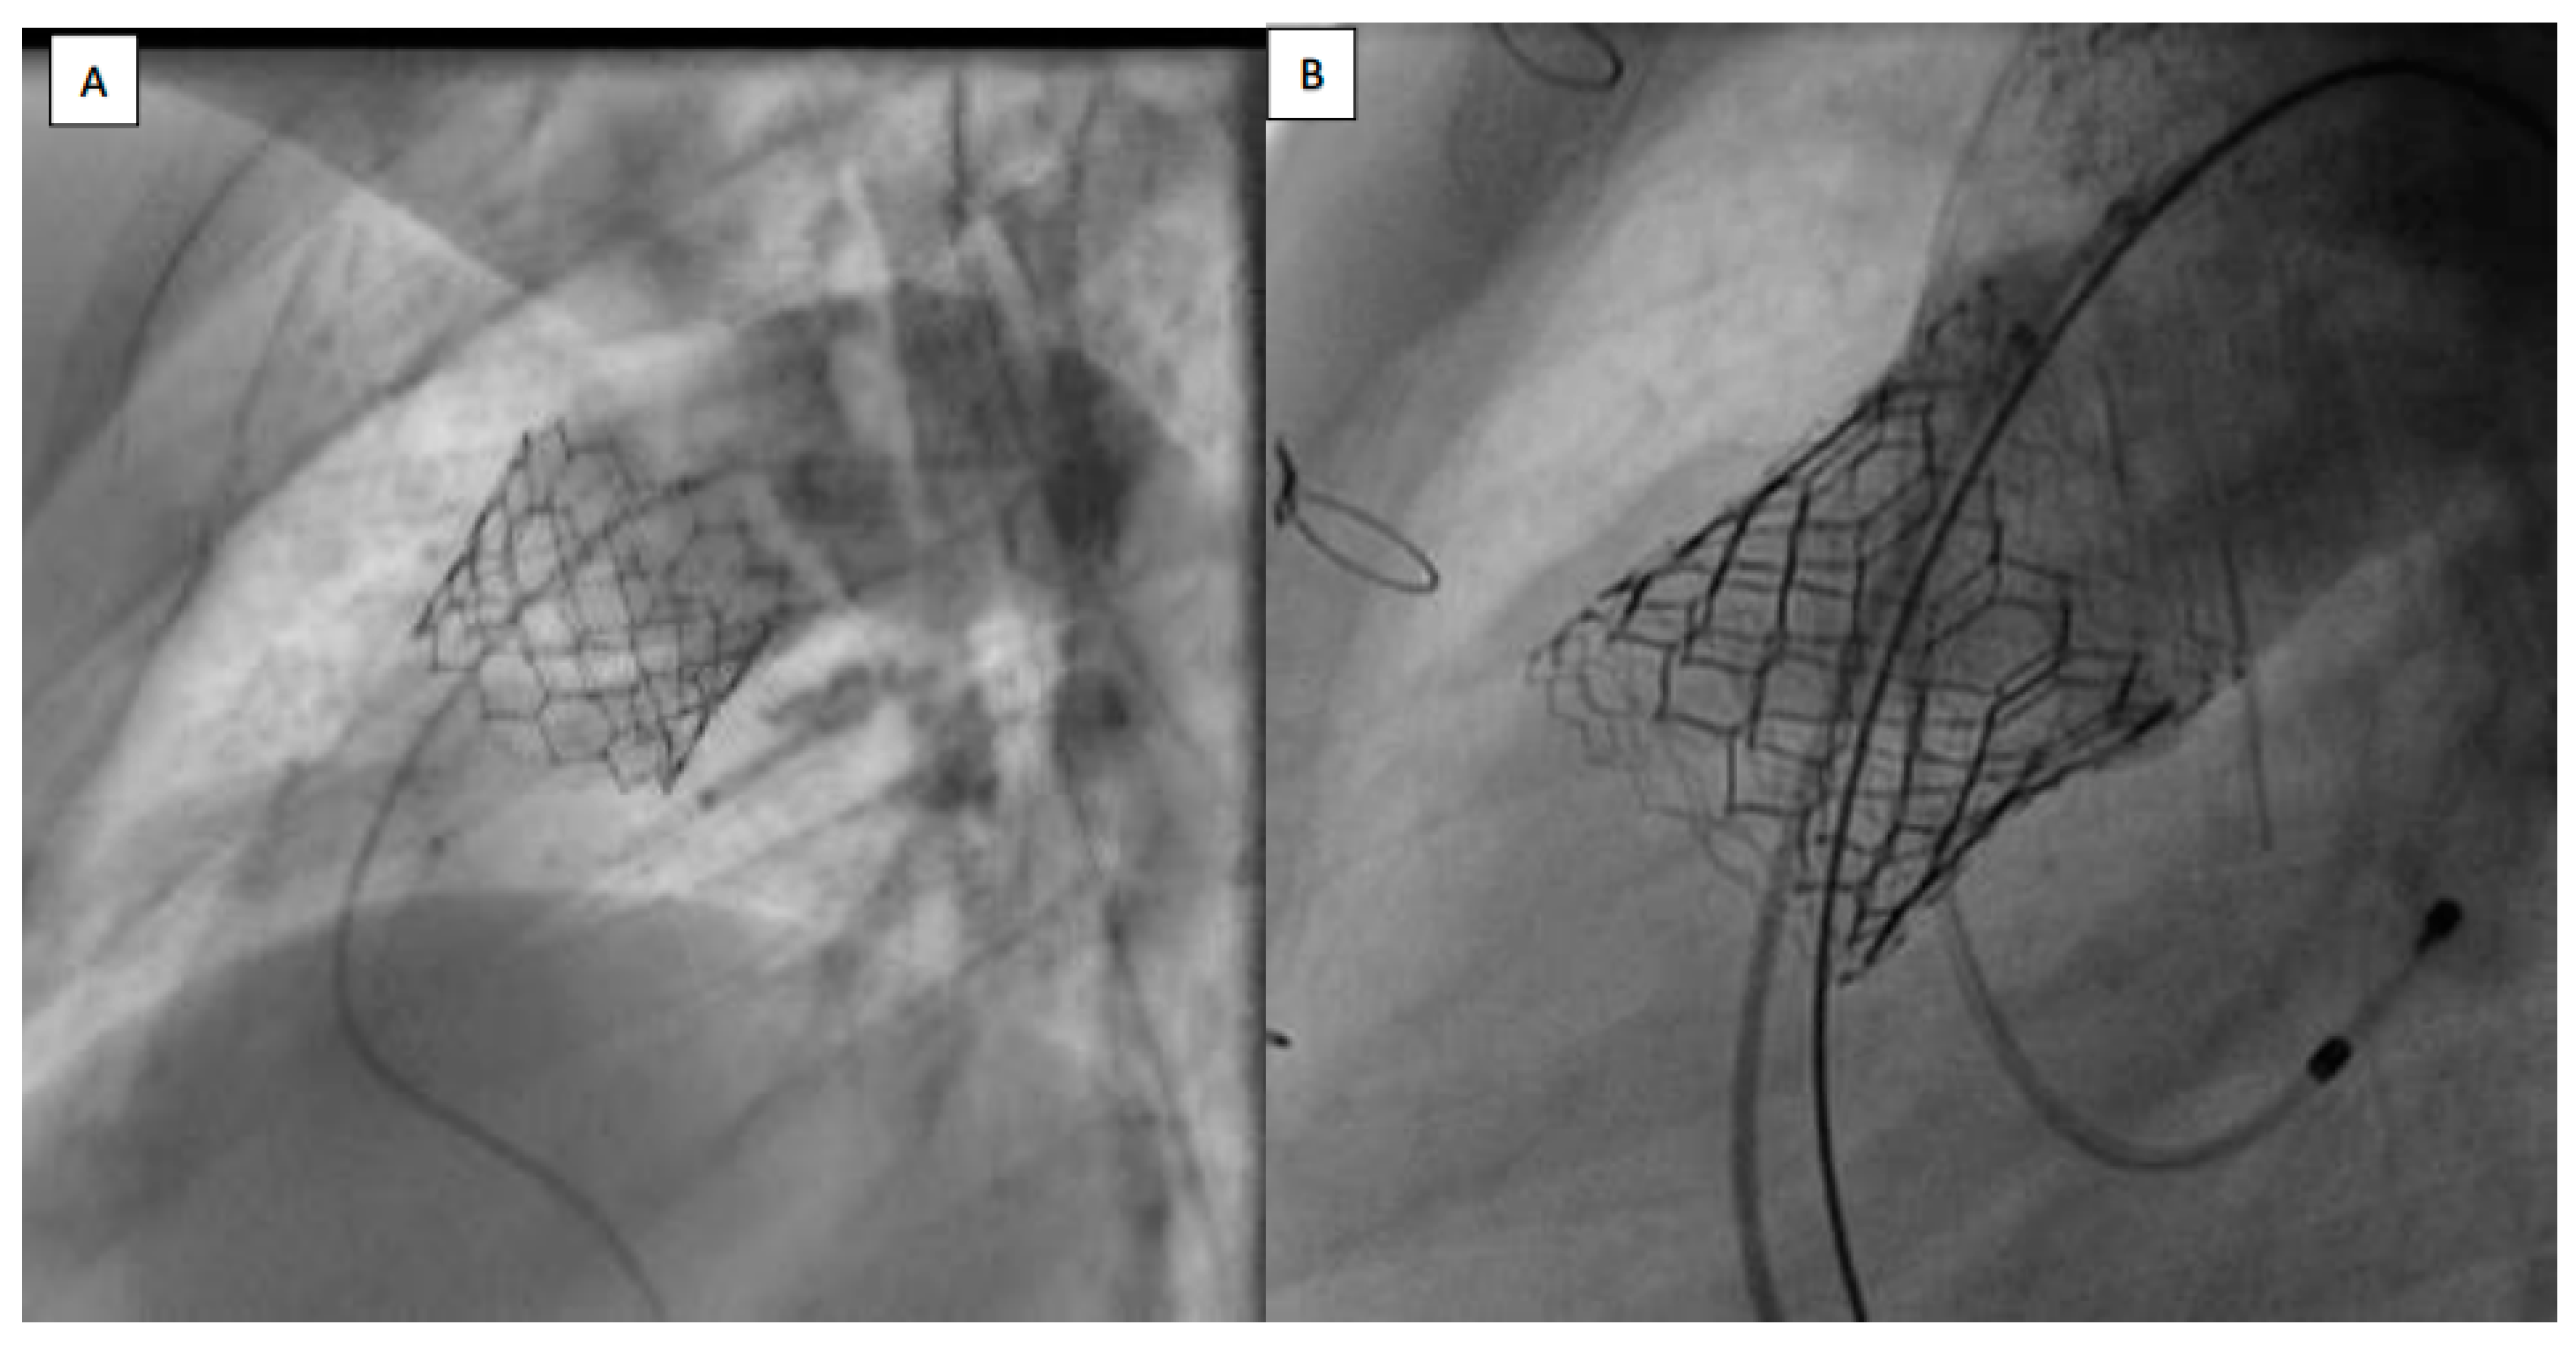

The PPVI technique was modified by using a large, long 65 cm GORE® DrySeal Flex Introducer Sheath (W.L. Gore & Associates, Inc., Flagstaff, AZ, USA) to safely advance the SAPIEN 3 valve into the landing zone along the right heart cavities [11]. Prestenting was avoided in case of regurgitant RVOT (conduit or native RVOT) without severe stenosis when a stable landing zone measuring less than 29 mm could be demonstrated during the preprocedural CT scan and during the compliant balloon testing [17]. Valves were delivered using a Commander® delivery system in all cases (Figure 1).

Figure 1.

(A) Sapien 3 valve, implanted without prestenting in native patched RVOT. (B) Sapien 3 valve, implanted with prestenting in native patched RVOT. RVOT: right ventricle outflow tract.